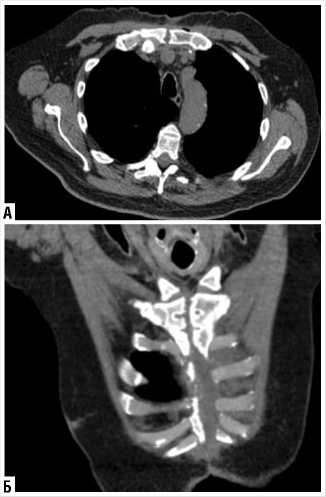

На контрольной КТ грудной клетки отмечено полное сопоставление рукоятки грудины, отсутствие признаков воспалительного процесса и скопления экссудата (Рис. 10 А, Б).

Рис. 10. Контрольное КТ грудной клетки после затягивания стернотомной раны после реконструктивно-восстановительной операции.